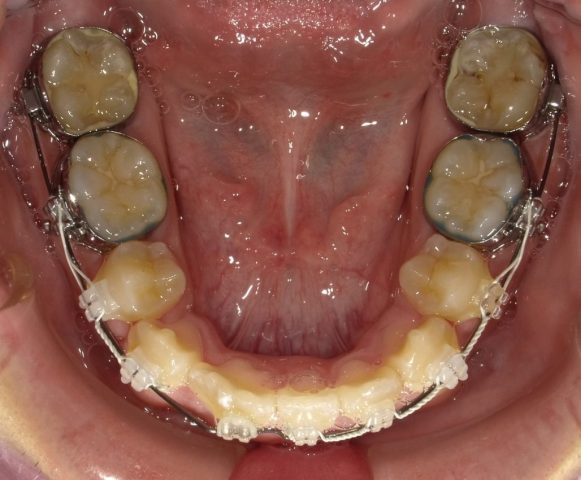

【下顎咬合面観】

2023年1月